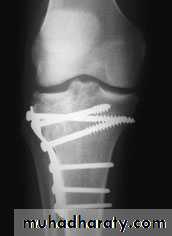

Tretment

Undisplaced fracturestreated conservatively:

Haemarthrosis aspiration and compression bandaging,

above knee cast for one months

followed by functional brace and physiotherapy.

For displaced fractures

treatment is by open reduction and internal fixation with

plate and screws as it is an intra articular fracture.

Complications :

1- Vascular injuries and nerve injuries.

2- Compartment syndrome (specially with severe condylar fractures).

3- Joint stiffness (prevented by early range of motion exercises).

4- Deformity

(Varus or Valgus), Valgus deformity are common complication.

5- Secondary osteoarthritis (due to residual depression, knee deformity or ligament instability) .